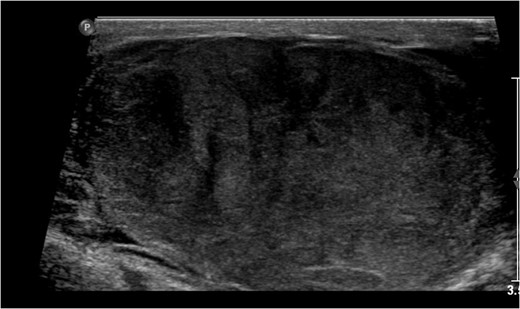

A 63-year-old gentleman who is a known case of dyslipidemia was presented to our Emergency Department with a right sided scrotal swelling and pain for 1 week. The patient had been having right testicular pain for the past 6 months on and off but never sought medical advice. On clinical examination, the patient had right scrotal swelling with epidydimal and cord tenderness and swelling, the cremasteric reflex could not have been assessed due to the large size of the scrotum with reactive scrotal wall edema. The patient underwent Doppler ultrasound which showed right testicular heterogeneous echotexture with nodular hypo-echoic areas (Fig. 1) with preserved vascularity. There was no evidence of testicular torsion or masses in that study. A provisional clinical correlation was made and the patient was diagnosed with right epididymo-orchitis and discharged home on oral antibiotics. Next day, the patient presented again to our ER with increased pain, swelling and erythema reaching the right inguinal area. So, the patient was admitted for administration of intravenous antibiotics. After 2 days of IV antibiotics, the patient’s condition was not improving which prompted the need of a CT scan. CT scan showed a heterogeneous enlarged right testis with twisting of the spermatic cord at the level of inguinal area and scrotal neck (Fig. 2). A diagnosis of testicular torsion was made based on these findings. The patient then underwent an urgent exploration with an inguinal incision which showed a hugely edematous cord, the incision was extended as Hockey-Stick incision and the right testis was delivered. The testis was dark, edematous, with no evidence of palpable testicular masses. The spermatic cord was twisted in 1080° clockwise fashion in three areas (Fig. 3). The first 360°, torsion was at the level of the deep inguinal ring, the second at inguinal part of the spermatic cord, and the third is just proximal to the testis. Right radical orchiectomy was carried out with high ligation of the spermatic cord at the level of deep inguinal ring, which was the site of normal, non-engorged cord. The procedure was completed with the extended inguinal incision with no violation of the scrotum, since the pathology was high in the inguinal area. The patient recovered very well with no complications.

Right testicular Doppler US showing hypo-echoic areas with heterogeneous echo-texture.